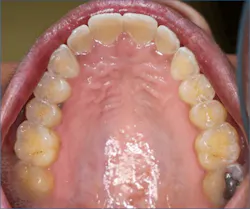

Dental erosion is a chemical process characterized by acid dissolution of dental hard tissue resulting in an irreversible loss of tooth structure. Acid destruction of the dentition occurs with both extrinsic and intrinsic factors. Extrinsic factors are caused by bacteria that produce acidic byproducts in persons that have diets high in sucrose and poor oral hygiene, or diets that are high in acidity. Intrinsic factors such as acid reflux or the purging associated with BN are also causative effects.5 Perimolysis is a specific form of tooth erosion that’s caused from intrinsic factors without bacterial involvement6 (figures 1,2).

Discolored teeth are the result of tooth erosion and loss of enamel, which is whiter in color than dentin, which is more yellow. Once the enamel is gone, a darker colored and weakened tooth remains that is subject to fracture and is more susceptible to tooth decay.

Dental patients with eating disorders may also present as physically healthy and be considered ASA I patients. Therefore, it is prudent for practicing dental hygienists and dentists to be familiar with the oral manifestations of eating disorders so that they can recognize the oral signs of an eating disorder and refer the patient for proper treatment.2,3,5,8 Particularly, identification of the early signs of periomolysis before more enamel is lost as seen in Figures 1, and 2 is considered optimal.